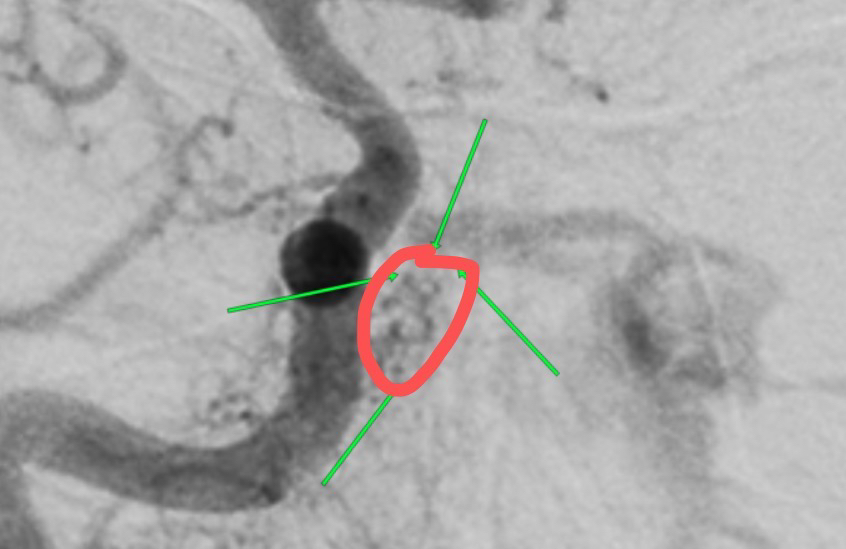

不能排除此处瘘口

瘘口?

左侧颈内动脉侧位,瘘口?

瘘口处